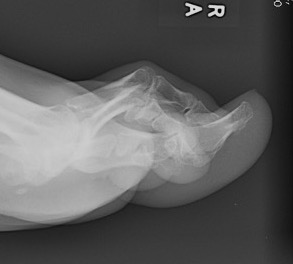

Cavus foot